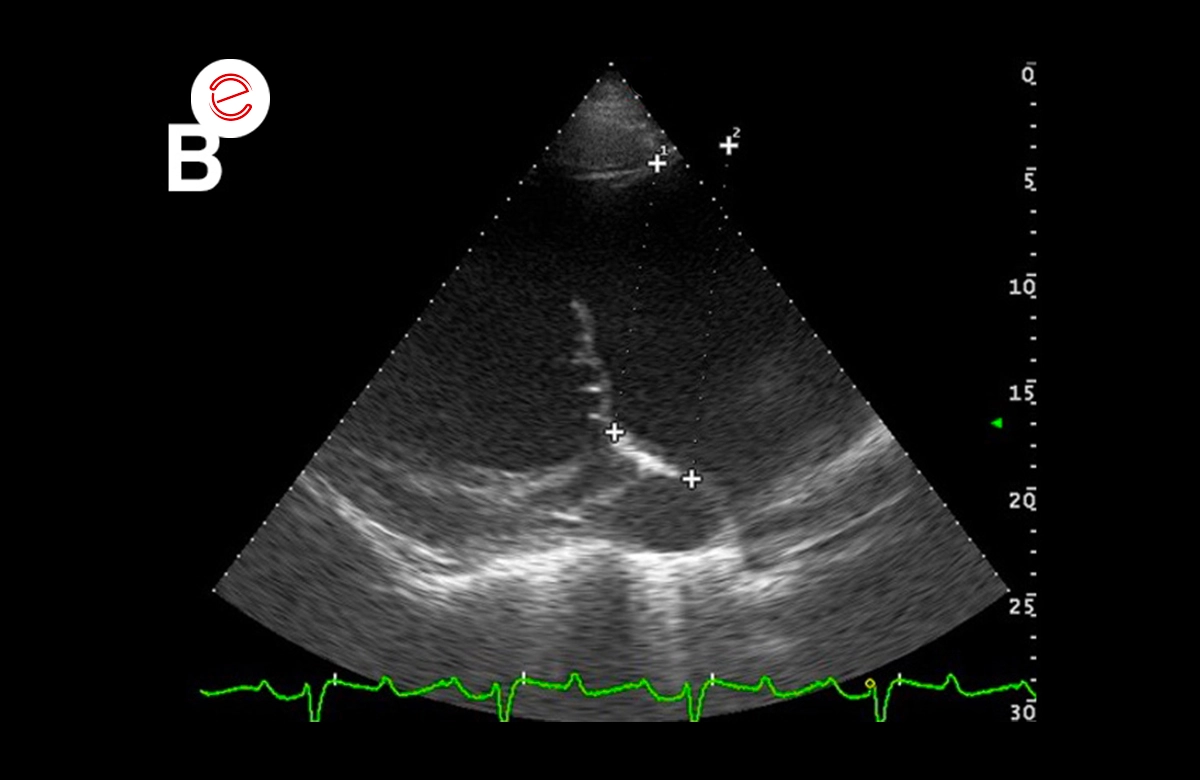

Right parasternal 4 chamber view (A) and left parasternal view of the left atrium and ventricle: significant dilation of the left atrium (v 166,4 mm; v.n 116 ± 7 mm) and the ventricle (systolic v 163.2 mm; v.n 112 ± 8 mm – diastolic v. 86.7) which present a globular aspect.

Right parasternal 4 chamber view (A) and left parasternal view of the left atrium and ventricle: significant dilation of the left atrium (v 166,4 mm; v.n 116 ± 7 mm) and the ventricle (systolic v 163.2 mm; v.n 112 ± 8 mm – diastolic v. 86.7) which present a globular aspect.